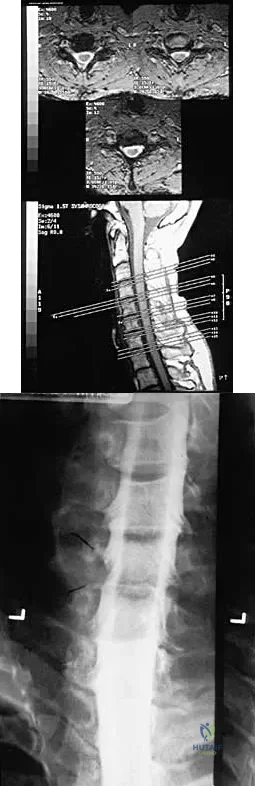

Question 64

A 32-year-old professional football player has disabling left arm pain in the C7 dermatome that has been increasing in severity for the past 2 months. Examination shows a positive Spurling test on the left side, but no changes in motor, sensory, or deep tendon reflexes. Because nonsurgical management has failed to provide relief, he has chosen surgery to allow him to complete his season. The MRI scan and myelogram shown in Figures 19a and 19b show minimal disk bulge, but a root cutoff is noted at the left C7 foramen. Electromyography demonstrates C7 nerve root irritation. Which of the following procedures will best optimize his chances for completing the season?

Explanation